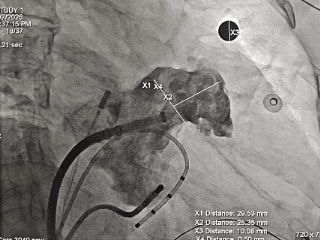

DSA下造影开口29.53mm,深度25.35mm;

-

房间隔穿刺点靠下,从轴向避免心耳上缘的压迫。

封堵器露肩4-5mm,在LAFDQ-29允许露肩范围内;

肩部压缩比为:8-11%,符合推荐压缩比8-30%,压缩合适。